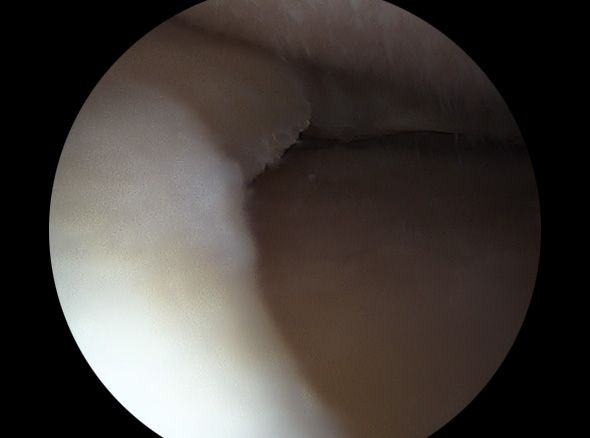

불안정한 반월상연골 부위를 내시경으로 확인하여 파열된 연골판을 꿰맴

반월상 연골판 파열 정도에 따라서 절제술, 봉합술로 나눠 수술을 결정합니다.